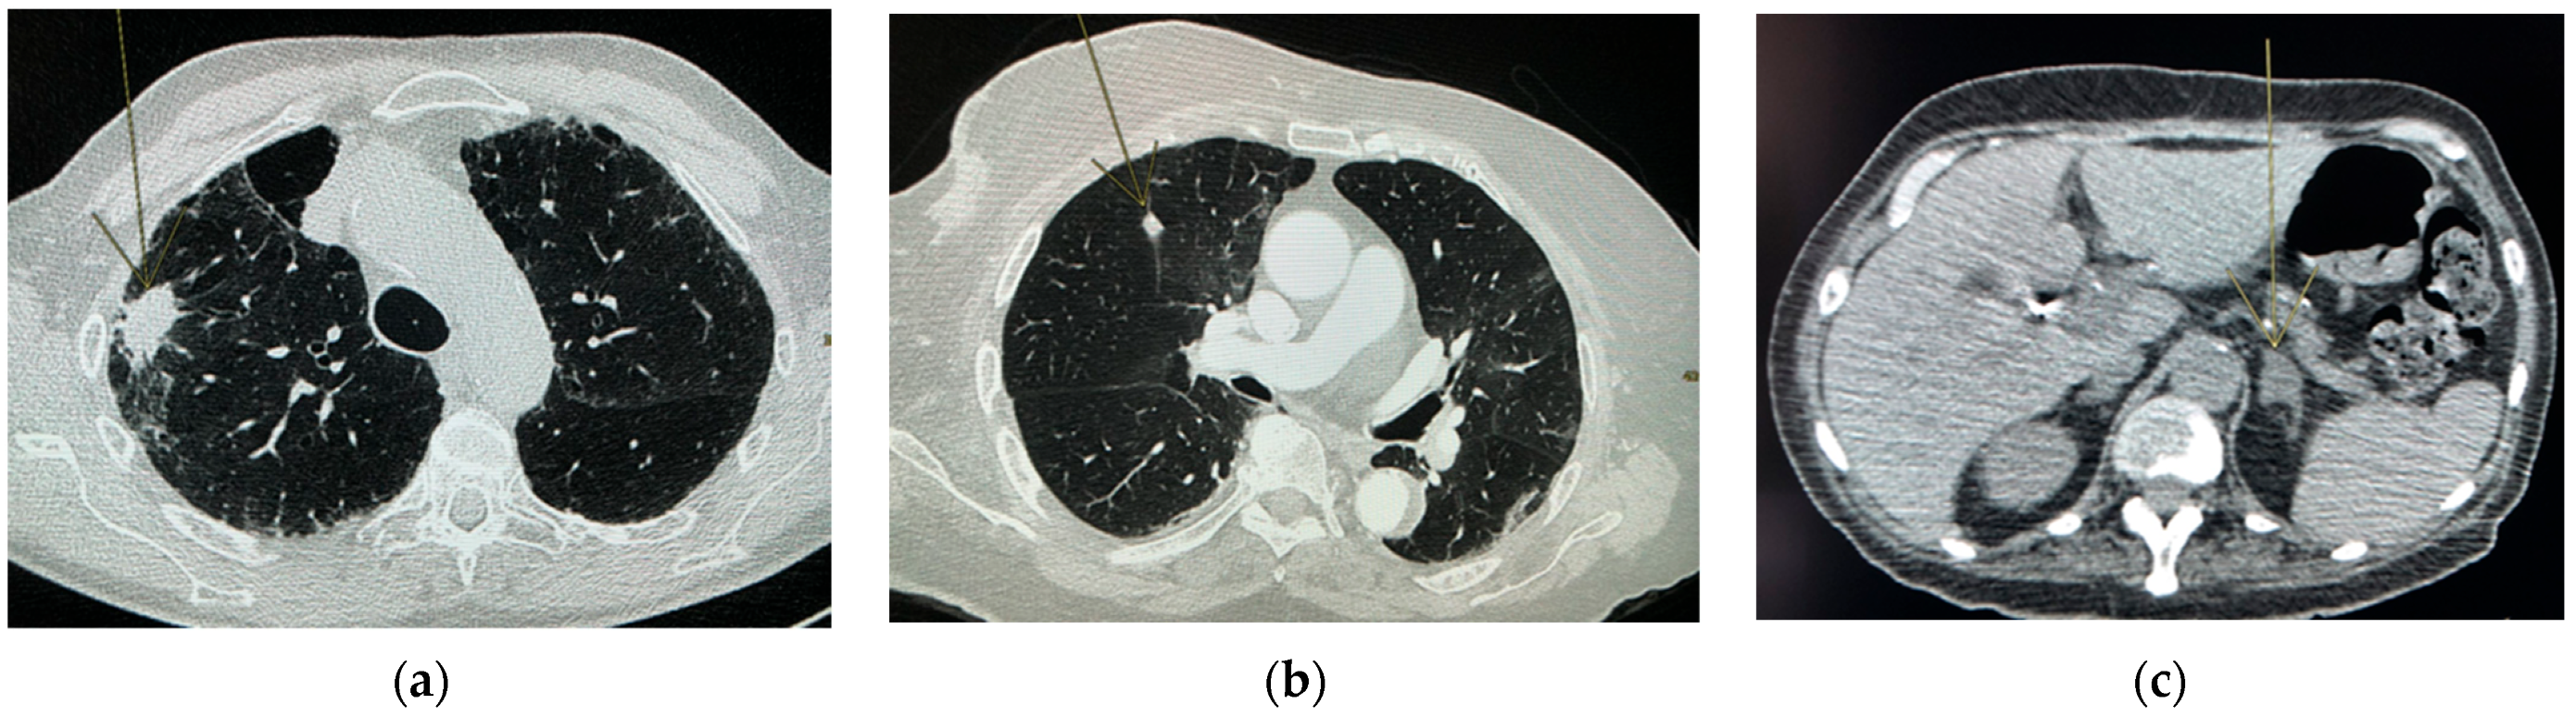

Risk Lesions